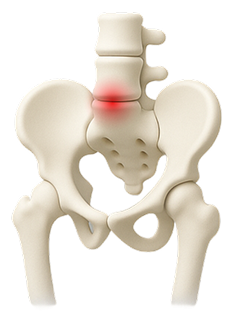

When the soft center of a spinal disc pushes through a crack in the exterior, it can press on nerves and cause pain.

Common Causes of Lower Back Pain

Lower back pain can stem from several underlying issues, including:

By realigning the spine and relieving pressure on nerves,

chiropractic care addresses the source of pain naturally and non-invasively.